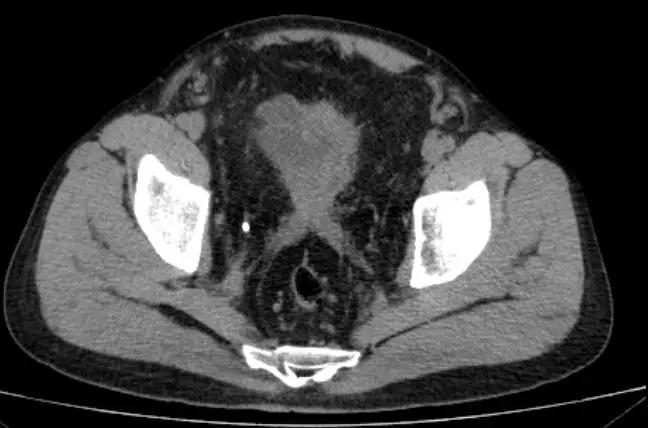

进一步完善泌尿系CT发现患者除了双肾重度积水,输尿管扩张之外盆腔有大量脂肪堆积

CT显示赵大哥双肾重度积水

盆腔脂肪明显增多,前列腺抬高,膀胱挤压变形